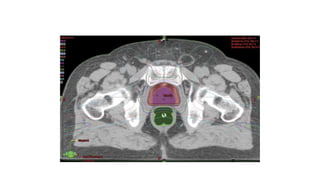

Forms of radiotherapy

• Conventional Radiotherapy

• Conformational Radiotherapy

• Intensity Modulated radiotherapy

Intensity-modulated radiation therapy (IMRT),is a form of three-

dimensional conformal radiotherapy (3D-CRT) and can provide

localization of the radiation dose geometrically and minimize injury to

surrounding structures.

Intensity modulated radiotherapy

• Three dimensional imaging and treatment planning

• CT-based images generate high-resolution 3D reconstructions of the

patient

• Computer controlled beam shaping can create arbitrary beam shapes

Radical external beam radiotherapy

• Indication:

• Age<70 yrs

• Stage T1b, T2, T3

• LN involvement detected by nodal sampling

• Risk of LN involvement ≥ 15%

• Documented SVI

• Gleason score ≥6

• PSA ≥ 20 ng/ml

• Treatment Volume- Prostate, Seminal Vesicle, prostatic urethra and

margin of 1-1.5cm for T1-T2 lesion and pelvic LNs to be included if the

lesion is T3.